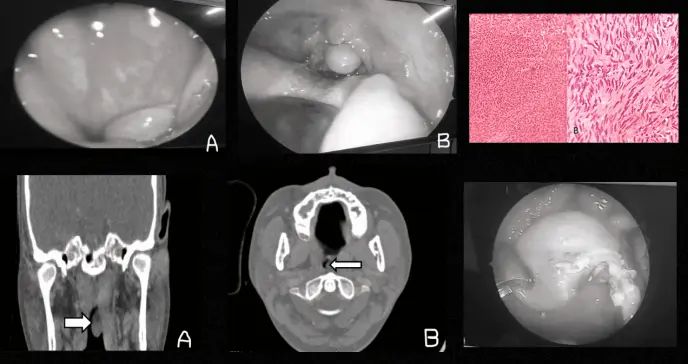

Imagen preoperatoria de la inflamación nasofaríngea. A. Lesión polipoidea vista desde la nasofaringe, detrás de la coana posterior. B. Desde la cavidad oral al presionar la lengua.

Los estudios radiológicos demostraron hallazgos concordantes con los observados durante la intervención quirúrgica. La tomografía computarizada con contraste evidenció una lesión polipoide bien delimitada, de atenuación tisular homogénea, que se originaba en la pared posterolateral izquierda de la nasofaringe.

Particularmente relevante fue la ausencia de extensión tumoral más allá de los límites nasofaríngeos, así como el realce homogéneo al contraste observado en el estudio.

Imágenes que muestran una lesión polipoidea que surge de la pared lateral posterior e izquierda de la nasofaringe. ( Imagen A : muestra (flecha) una masa polipoidea que surge de la nasofaringe en el plano coronal. Imagen B : muestra (flecha) una masa polipoidea que surge de la nasofaringe en el plano axial.

El análisis anatomopatológico reveló una lesión bien delimitada aunque no encapsulada, localizada bajo la mucosa faríngea. Microscópicamente, destacaba la presencia de células fusiformes dispuestas en patrones variables, con áreas focales de empalizado nuclear.

Celularidad homogénea con empalizada nuclear